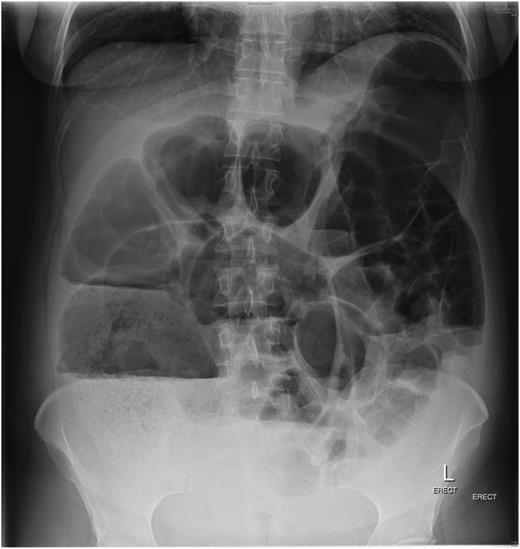

The patient, a 34-year-old female, developed symptoms consistent with pseudo-obstruction on Day 3 post-emergency Caesarean section, which was performed for foetal distress and possible placenta abruption. An abdominal X-ray was performed which showed a significantly dilated colon (Fig. 1), and the diagnosis of pseudo-obstruction was again confirmed on computer tomography (CT) scan of the abdomen which showed a caecum measuring 9.8 cm transversely (Fig. 2). Emergency colonoscopic decompression with the insertion of a flatus tube was performed and medical management, including cessation of opioids, anticholinergics and correction of electrolyte abnormalities, was commenced.